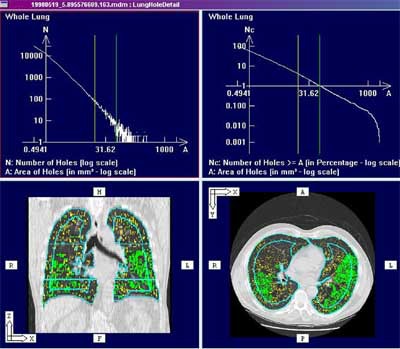

| Screen shot of histogram-based analysis embedded in PASS (Pulmonary Analysis Software Suite). Built in the University of Iowa Lab, the PASS lung image display and analysis software is being commercialized by startup firm VIDA Technologies. Image courtesy of Eric Hoffman, Ph.D, who is a principal in the company. |

Beyond the airways, Hoffman and colleagues have developed methods of measuring the lung parenchyma. In a project for the National Emphysema Trial, for example, the group came up with close to 200 measurements derived from the density histogram, in an effort to predict outcomes in lung reduction surgery.

Another technique, the adaptive multiple feature method (AMFM), draws its values from 26 different mathematical formulations of grayscale formatting of the lung, including entropy, fractal dimensions, run length, coding, and cunis of the histogram, he said. A Bayesian classifier is then used to determine the "ground truth."

The Bayesian classifier accounts for all of the measurements for the different pathologies, and then finds groupings of, say, 3 to 5 features that separate one tissue type from another. It has succeeded in doing so to the tune of 90%-95% specificities and sensitivities for the identification of tissue types such as ground glass nodular, bronchovascular honeycombing, etc., and the group recently extended the 2-D features into 3-D.